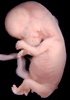

Human Embryo

Carnegie Stage 23 (56 post-ovulatory days)

Most embryos at stage 23 are approximately 56-57 postovulatory days old and measure 23-32 mm in length. Distinguishing criteria for this stage include fusion of the eyelids at the medial and lateral margins, clear distinction of the subdivisions of the upper and lower limbs, the forearms appear at or above the level of the shoulders, the superficial vascular plexus of the head is very close to the vertex, and the external genitalia are well developed but not always sufficiently to distinguish the embryo's sex.

(NOTE: These specimens are late stage 23.)